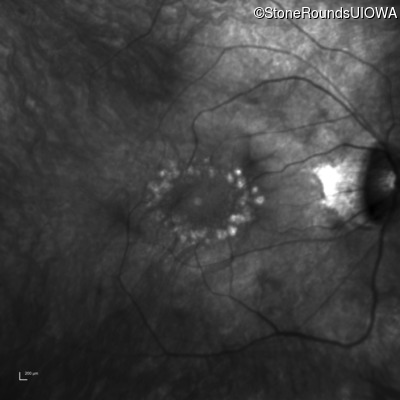

Infrared Fundus Photograph - Right - 20/25

Exemplar